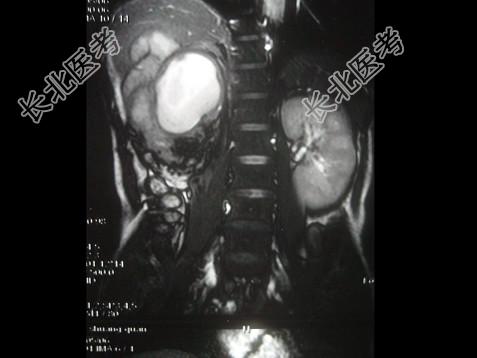

- 单项选择题女,43岁, 右腰部疼痛不适2年余,加重3天, CT及MRI检查如图,应诊断为 ( )

A、右肾癌

B、右肾错构瘤合并出血

C、右肾脂肪瘤

D、右肾脂肪肉瘤

E、右肾海绵状血管瘤